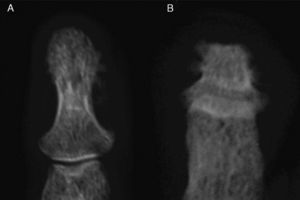

Clinical PresentationThe case is a 30-year-old male patient with a history of primary pulmonary hypertension without a shunt and followed by pediatric cardiology ever since. He had no other history of importance, including rheumatic disease or psoriasis. At age 29 he started presenting episodes of symmetric, additive polyarthritis which affected knees, ankles, shoulders, wrists and metacarpophalangeal joints, with important functional limitation. Physical examination found, in addition to generalized cyanosis and acropachy, no skin or nail lesions suggestive of psoriasis. Laboratory analysis found normal acute phase reactants, negative rheumatoid factor and positive low titer anti-CCP antibodies in a single determination. X-rays showed acroosteolysis of the distal phalanges of the hands and feet, severest in the latter, in which some of the phalanges adopted the form of a pyramid or had a flattened end, with important bone neoformation in both locations, especially the hands (Figs. 1 and 2). Both wrists observed, in addition to radiocarpal and intercarpal joint impingement, especially of the left side, no erosions. Long bones (tibia, peroneal, radial) had a cottony cortex and periosteal separation compatible with periostitis. A bone scyntigraphy showed moderate uptake in the distal phalanges of both hands, as well as right wrist and radium with a theoretical zone in the left semilunar.

Hand X-ray (A) in which there is a periosteal reaction on the radius. There is distal widening with hypertrophic changes and areas of osteolysis, with a good example on the right fourth finger. Juxtaarticular demineralization. Feet X-ray (B) observing marked destruction of the distal phalanges, some with flattened morphology and distal hypertrophy with bone proliferation. There is marked deformity of the fingers.